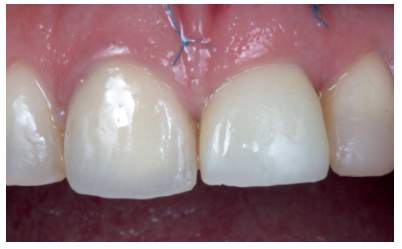

Tras 14 semanas se retiró el provisional, apreciando una correcta posición del margen gingival, con una cobertura de la recesión del 100%, un mantenimiento íntegro de las papilas y un correcto perfil de emergencia (Figuras 14 y 15). No obstante, desde una vista oclusal se evidenció una falta de volumen vestibular respecto al diente adyacente. Se comenzó a trabajar con la corona provisional, con incrementos progresivos de composite en el perfil subcrítico, hasta conseguir un volumen similar al diente 1.1. Estos incrementos fueron realizados cada 15 días (Figura 16)13.

Tras conseguir un volumen de tejido óptimo mediante el manejo del provisional (Figura 17), se realizó un primer escaneado del maxilar con la corona provisional atornillada para obtener la anatomía (Figura 18) y, posteriormente, un segundo escaneado sin la misma, registrando de forma precisa los contornos gingivales y el perfil de emergencia conseguido (Figura 19), así como la posición del implante mediante el scan body (Figuras 20 y 21). Para un correcto duplicado del perfil de emergencia, se procedió a escanear la corona provisional fuera de la boca (Figuras 22 y 23), evitando tener que realizar la técnica clásica de un transfer individualizado17. Estos registros fueron enviados al laboratorio protésico, el cual diseñó una estructura metálica sinterizada postmecanizada (Figura 24). Una vez realizada de forma satisfactoria la prueba de la estructura (Figura 25), se tomó el color de la restauración (A2 guía VITA) mediante un filtro de luz polarizada (Figura 26). Estos registros se enviaron de nuevo al laboratorio protésico para la finalización de la corona implantorretenida sobre los modelos impresos (Figuras 27 y 28). Previo a la colocación de la corona definitiva, se comparó el perfil de emergencia de la corona provisional con la definitiva, viendo la similitud entre ellas (Figura 29), consiguiendo así preservar los perfiles mantenidos desde el día de inicio del tratamiento.